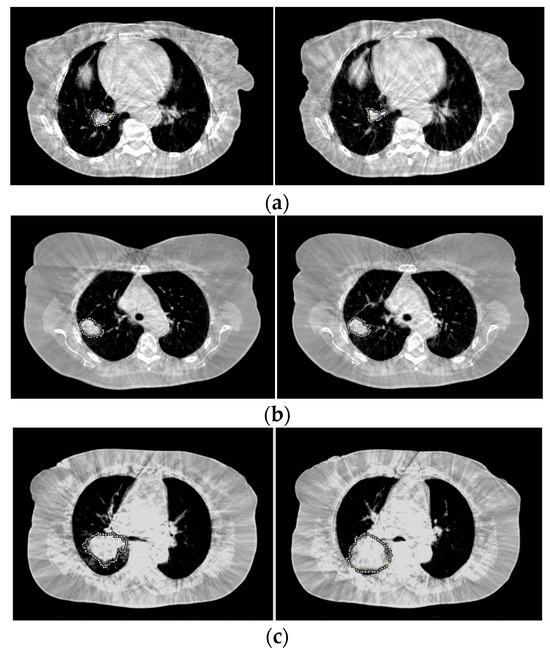

2.2. Image Analysis

2.3. Tumor Response Evaluation Parameters

2.4. Radiologic Assessment of Tumor Response